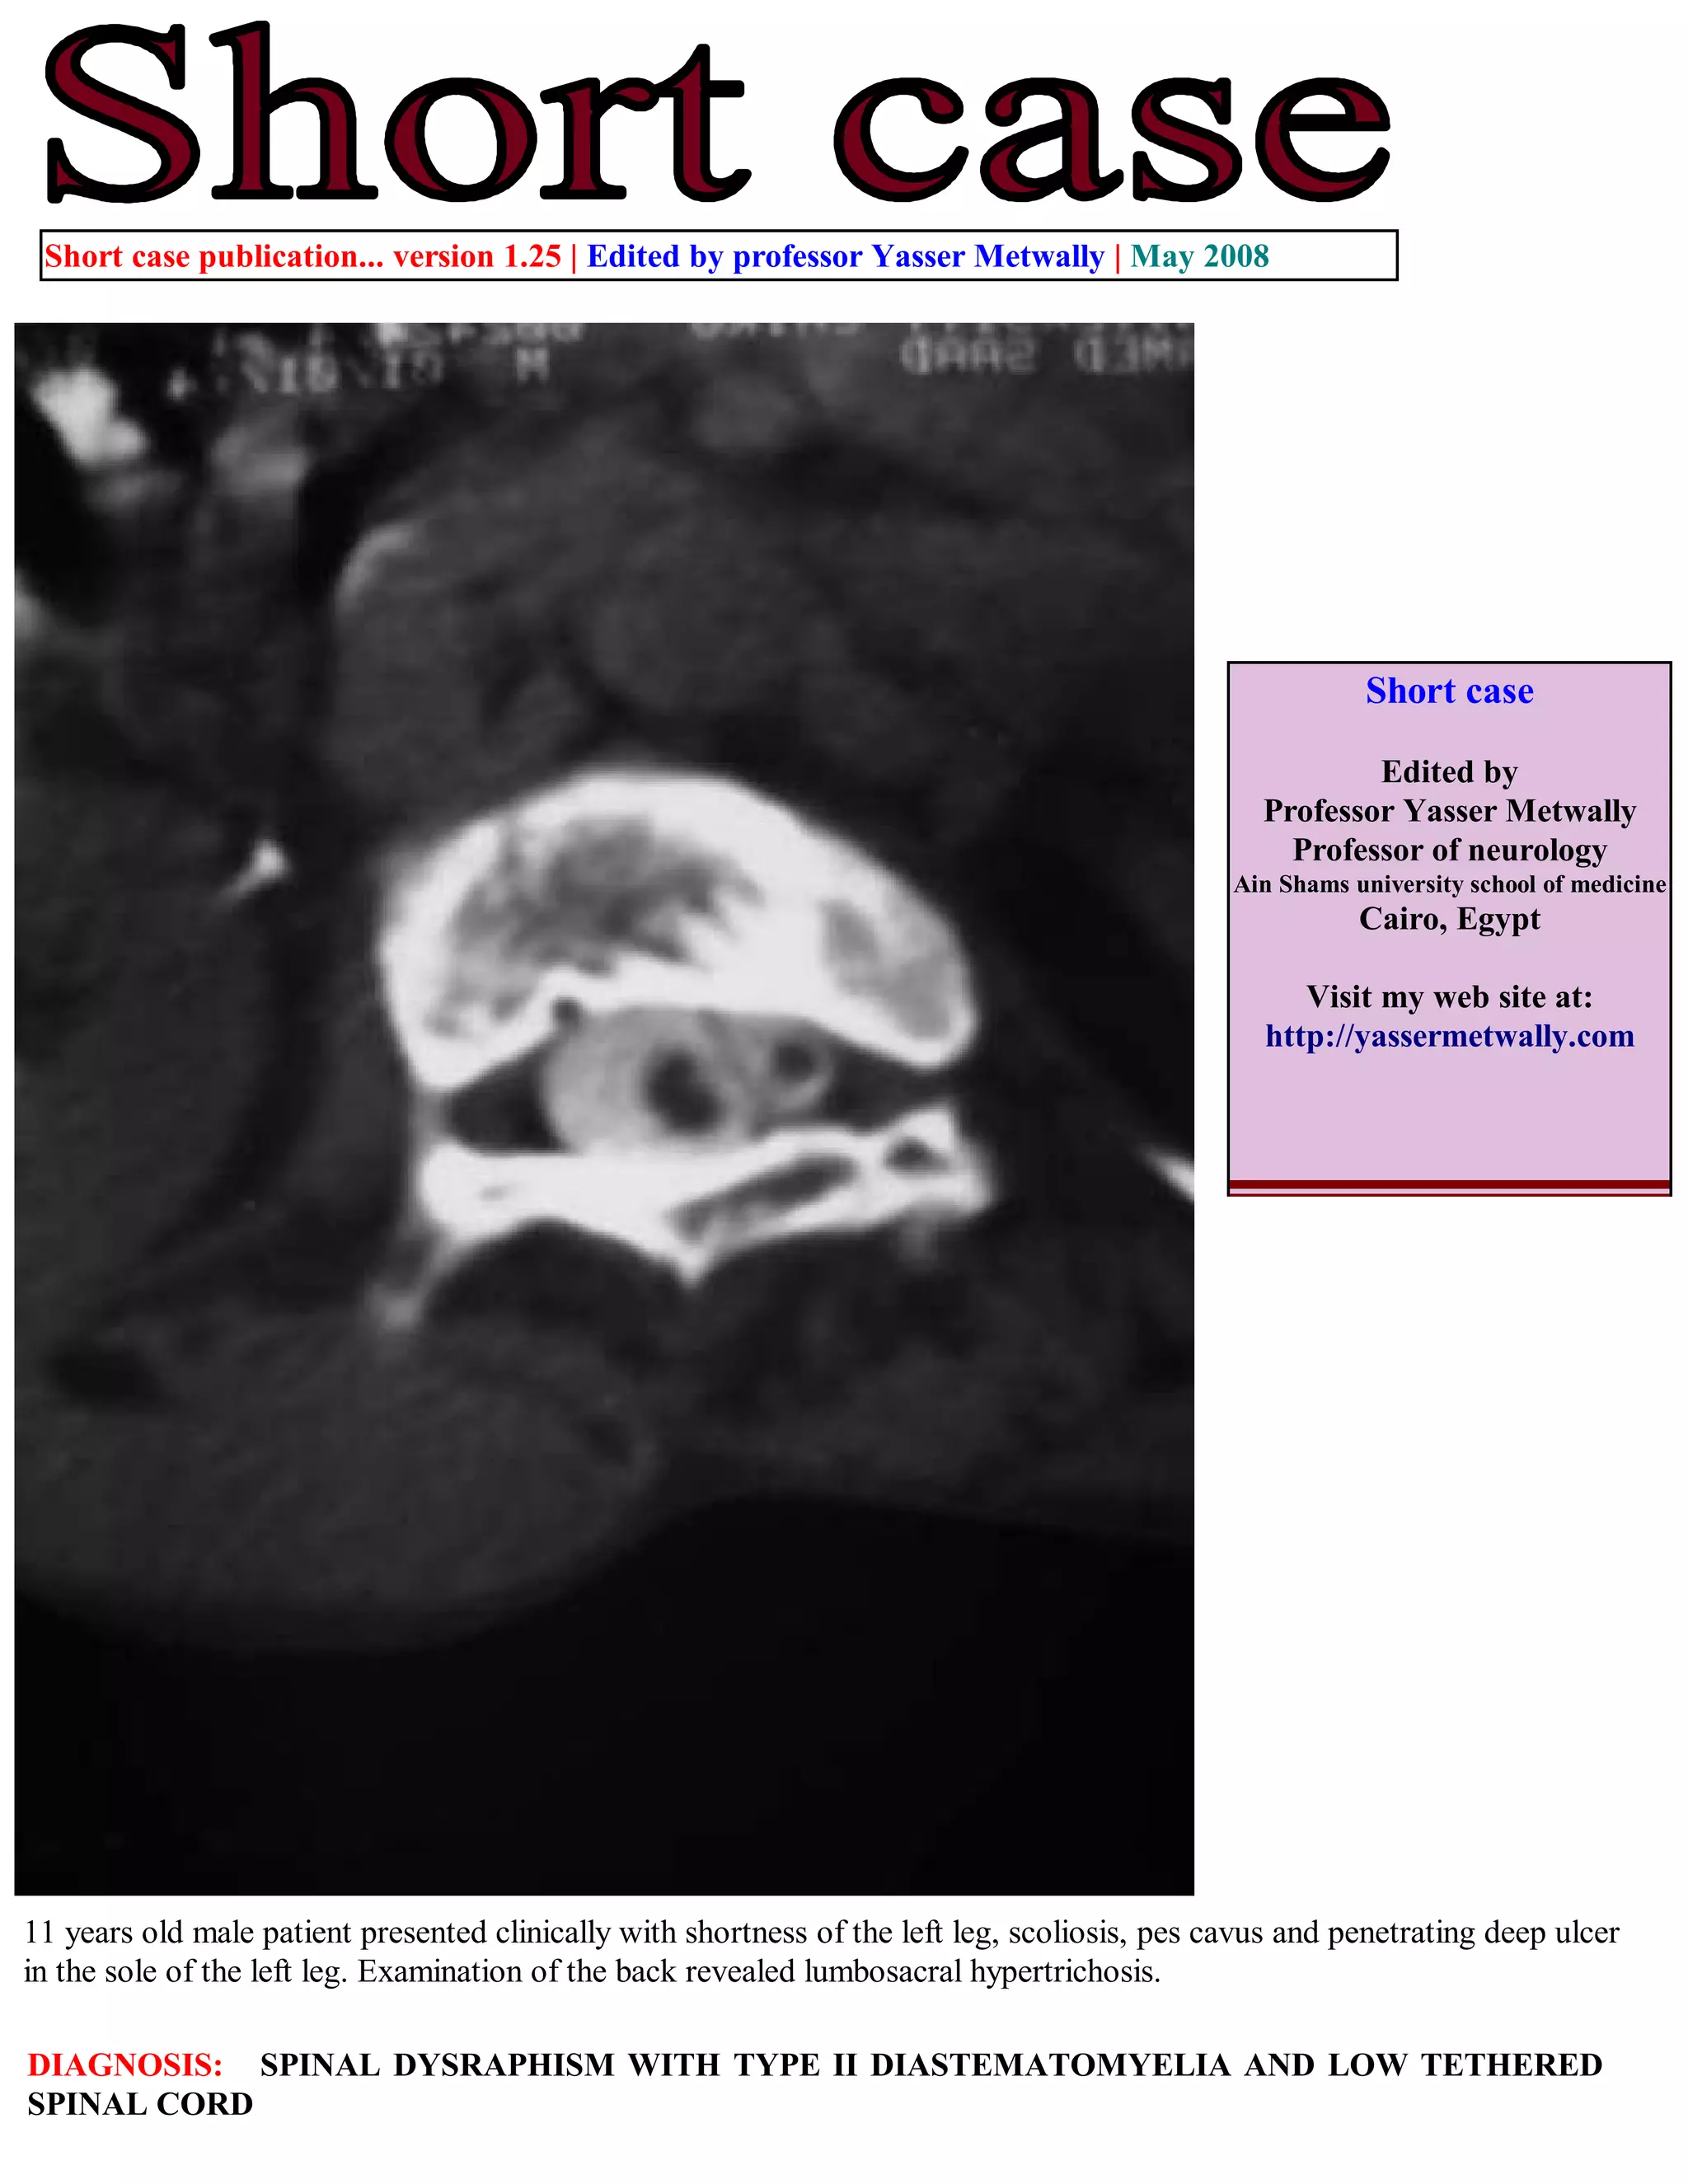

A 11-year-old male patient presented with shortness of the left leg, scoliosis, pes cavus, and an ulcer on his left foot. Examination revealed hair growth on his lower back. He was diagnosed with spinal dysraphism, a type II diastematomyelia, and a low tethered spinal cord based on CT myelography findings of a split, low-lying spinal cord within a dilated fluid space. The document provides information on accessing additional case publications and references a textbook on neuroradiology.